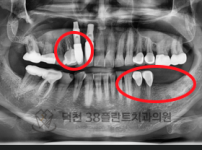

치료전후